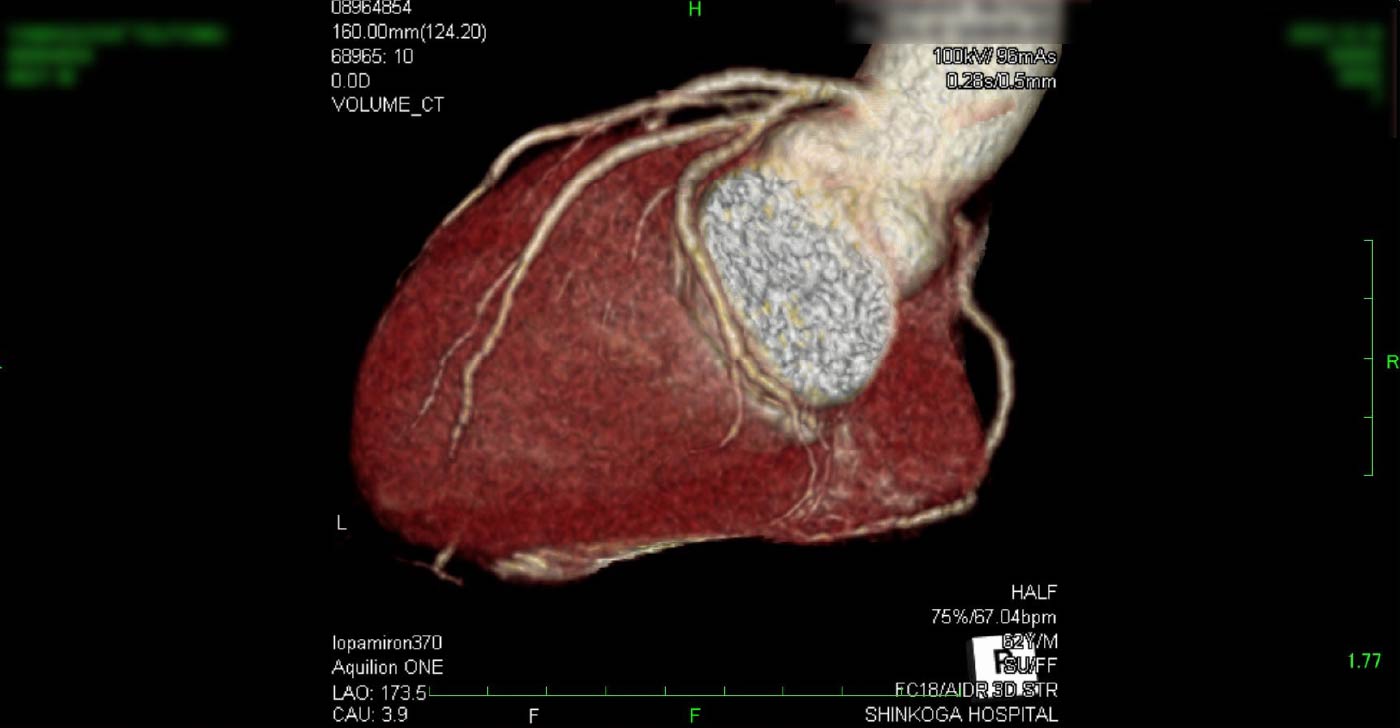

進行期 造影心臓CT 重症心筋虚血症例

冠動脈CT

狭心症を安全に診断あるいは除外する!

連携施設の新古賀病院で速やかに実行可能です。

冠動脈CT 冠動脈CT 冠動脈CT 冠動脈CT 冠動脈CT 冠動脈CT 冠動脈CT 冠動脈CT 冠動脈CT 冠動脈CT 冠動脈CT 冠動脈CT 冠動脈CT 冠動脈CT